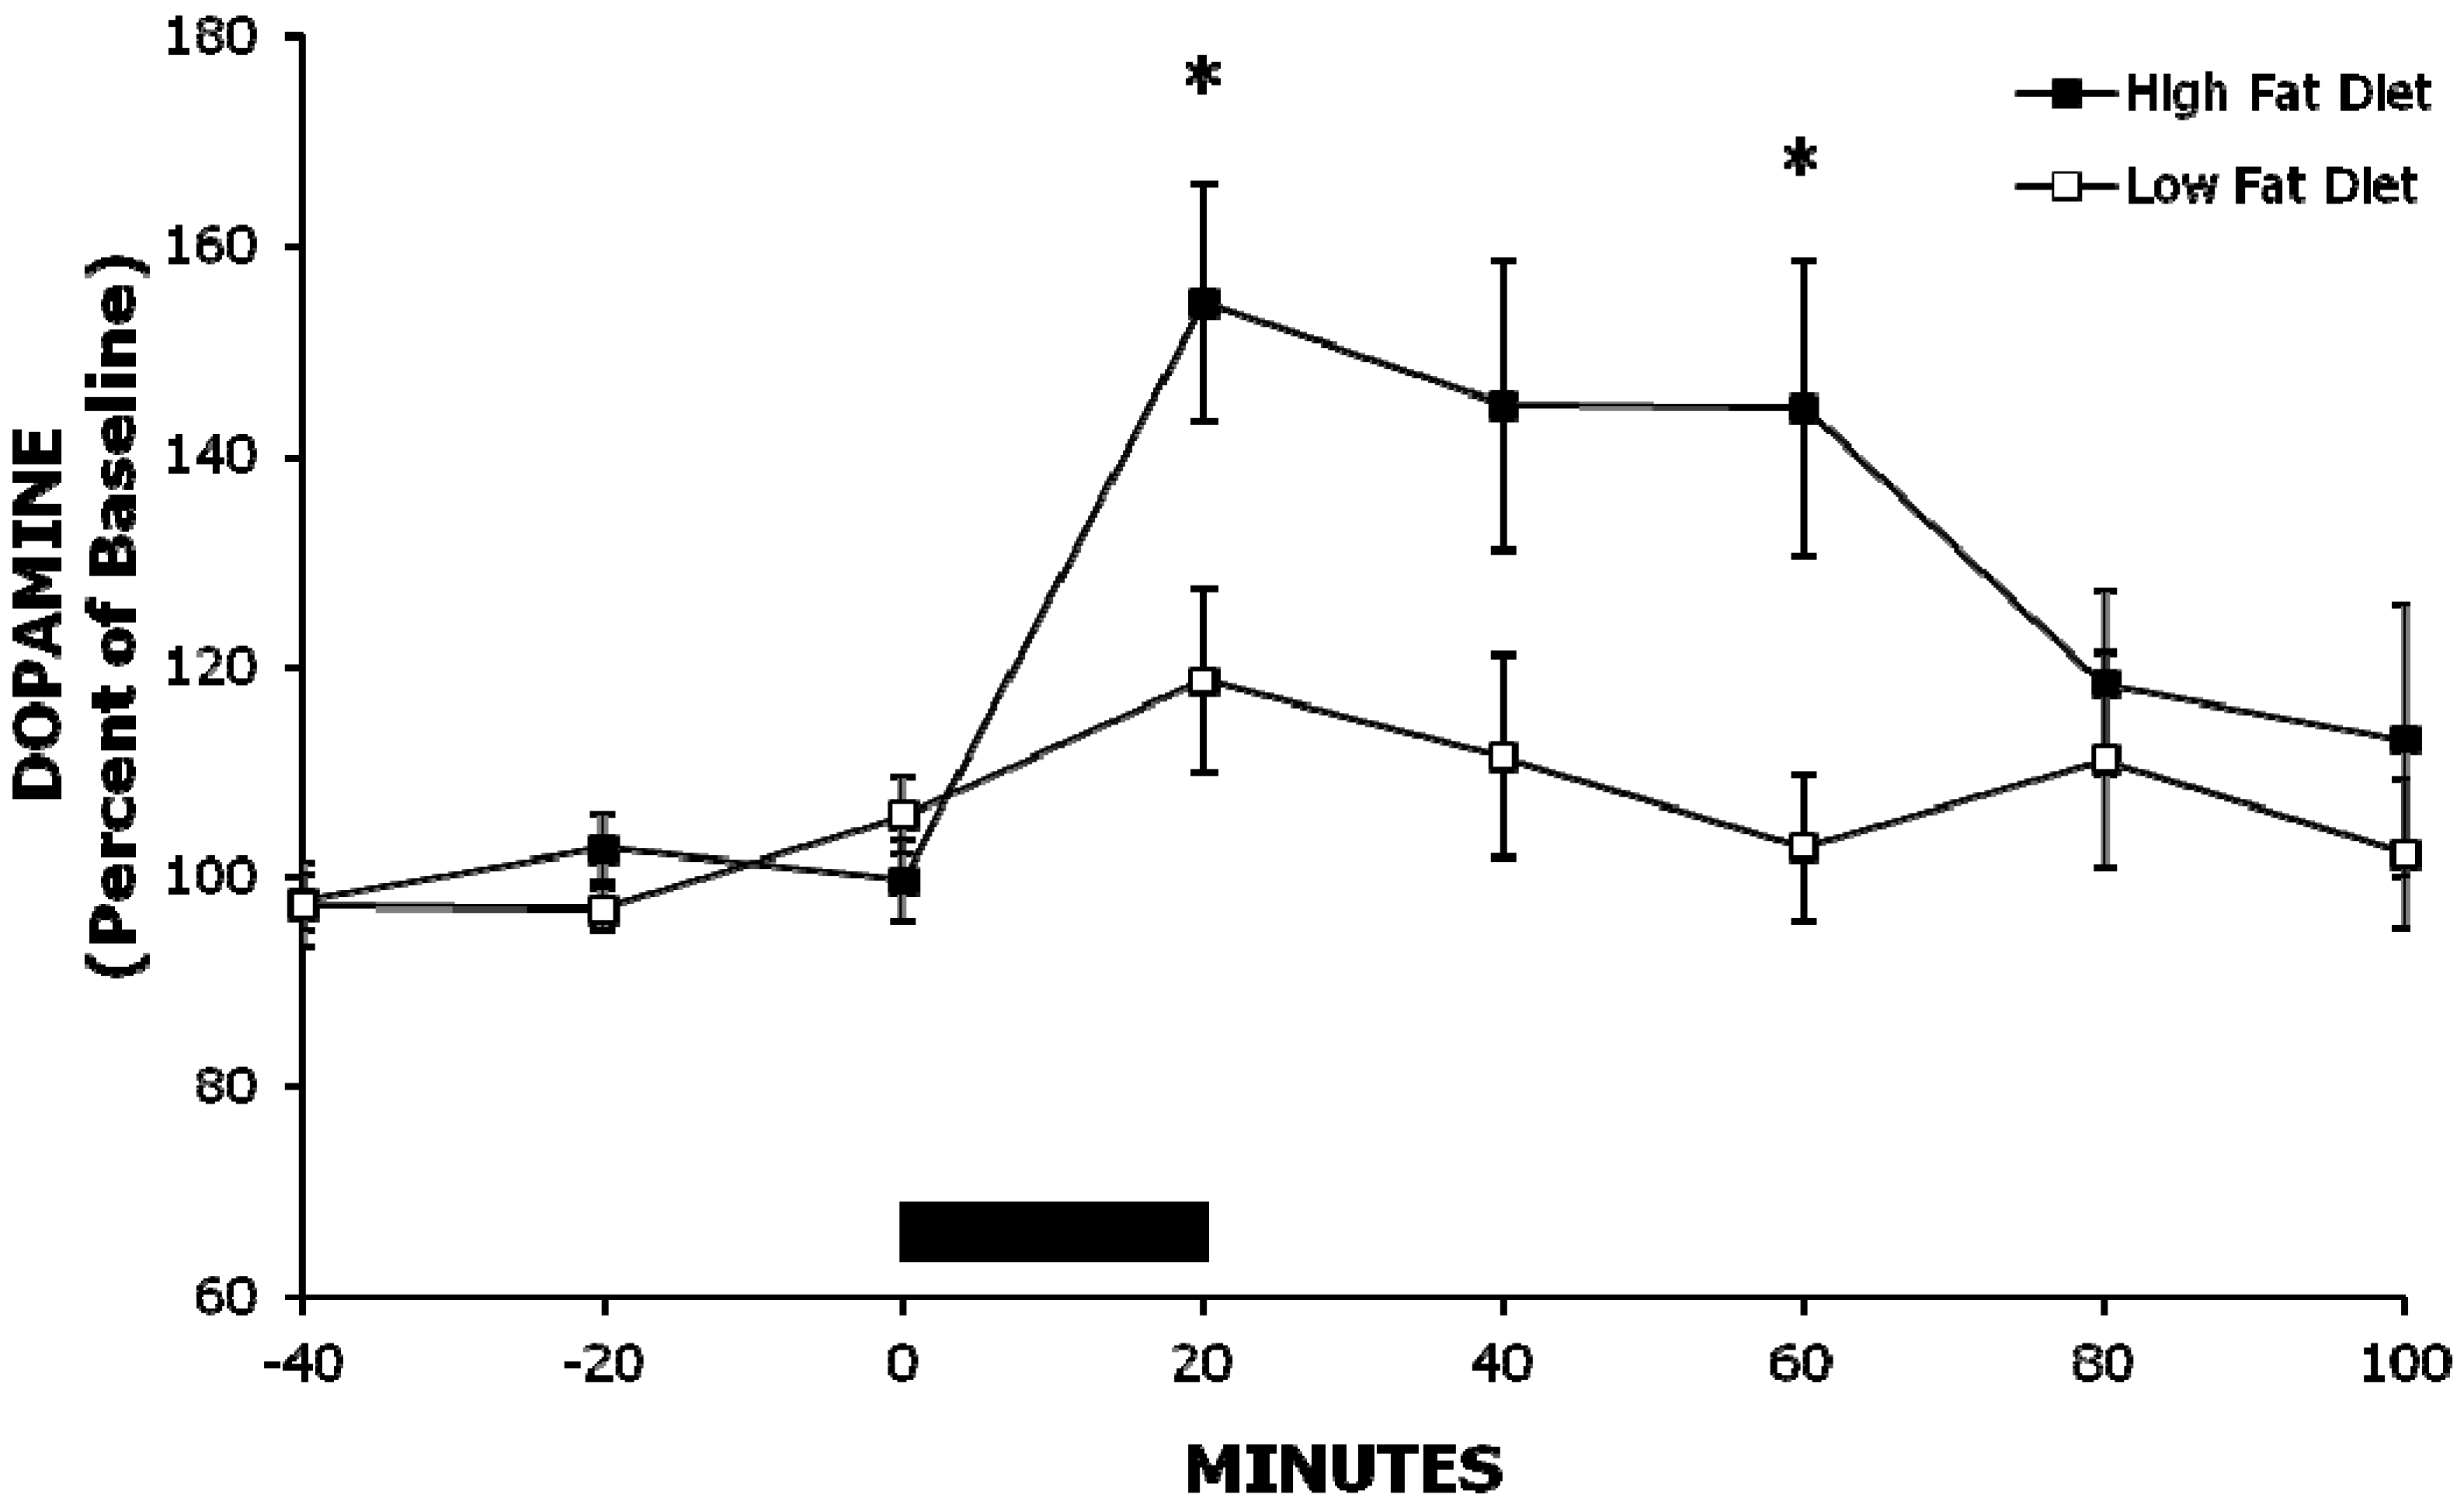

2.1. Experiment 1: A High-Fat Meal Increases Extracellular NAc DA Levels More than a Less Palatable Low-Fat Meal

| Experiment 1 | Baseline | 20 min | 40 min | 60 min |

| DOPAC | ||||

| High-Fat Meal | 99 ± 2% | 124 ± 4% | 125 ± 5% | 122 ± 7% |

| Low-Fat Meal | 102 ± 1% | 113 ± 5% | 115 ± 5% | 112 ± 6% |

| HVA | ||||

| High-Fat Meal | 102 ± 3% | 117 ± 4% | 126 ± 4% | 130 ± 7% |

| Low-Fat Meal | 100 ± 2% | 112 ± 5% | 119 ± 6% | 120 ± 6% |